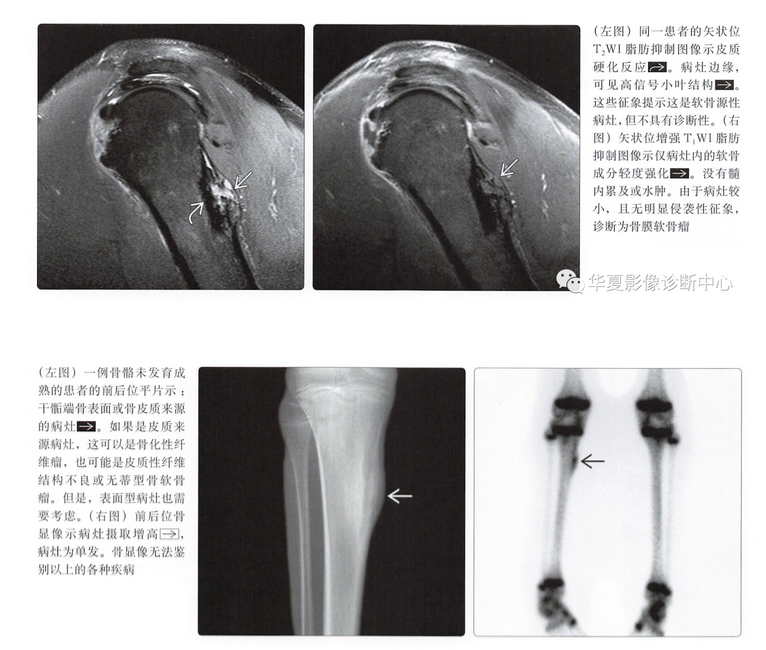

平片表现

- 骨皮质扇形凹陷

- 硬化边

- 致密性骨膜反应,尤其是在病灶近端、远端

- 病灶远端、近端骨皮质杯状改变

- 基质钙化(75%)

- 软组织肿块

骨膜骨肉瘤

- 中度恶性的表面型骨肉瘤

- 与骨膜软骨瘤发病部位相同

- 与骨膜软骨瘤几乎有相同的平片表现

- 附着骨皮质有相似的扇形塌陷倾向

- 常可见到基质钙化

- 骨样特点有时难以与软骨鉴别

高级别表面型骨肉瘤

- 罕见的高级别骨肉瘤

- 比骨膜软骨瘤生长更快

- 病灶中央可见骨样结构

- 可以有但不总是有骨皮质扇形凹陷

骨旁型骨肉瘤

- 明确的骨旁型骨肉瘤不应与骨膜软骨瘤相混淆

- 病灶内分化良好的骨质与附着骨呈附着样表现

- 常有髓质受累

- 常见发病部位不同:位于股骨远端、胫骨近端

- 表面型病灶彼此之间常常难以鉴别

- 平片上难以鉴别早期软骨样结构和骨样结构

- 骨旁型骨肉瘤可通过分化良好的骨质成分鉴别,如分化差则常常不易鉴别

- 生长迅速是高级别表面型骨肉瘤的鉴别点

- 骨膜骨肉瘤与骨膜软骨瘤在平片鉴别相当困难